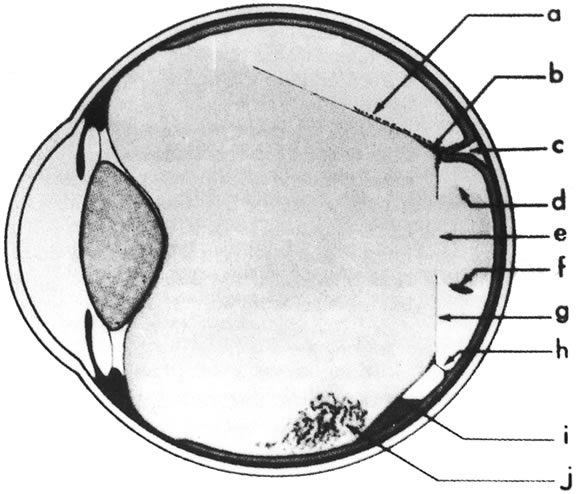

The vitreous of the normal human eye weighs approximately 4 g and occupies a volume of almost 4 ml. The precise weight and volume vary with the age and the size of the eye. The vitreous body is spherical with a depression in the anterior surface, the patellar fossa, corresponding to the posterior surface of the crystalline lens. Larsen1 ultrasonically measured the axial length of the vitreous body in 926 children. He noted that the mean value in newborns was 10.48 mm in boys and 10.22 mm in girls. A sex difference of 0.23 to 0.38 mm greater mean length was noted in males at birth and persisted throughout the growth period. By the age of 13 years, when the axial growth of the vitreous body is essentially completed, the average length was 16.09 mm in males and 15.59 mm in females. Larsen further noted that the relationship between vitreous length and refraction was already established by 1 year of age.

The vitreous body can be divided into two zones or regions. The more peripheral zone, the cortical vitreous, encases the medullary vitreous. The cortical vitreous consists of a relatively more condensed, fibrillar vitreous. Although the cortical vitreous represents only 2% of the total vitreous volume, it is the metabolic center of the vitreous body, because it contains the hyalocytes.2,3 Another connective tissue cell, the fibrocyte, is also found in the cortical vitreous. Most of the vitreous body, the medullary vitreous, is essentially a cell-free mixture of collagens and hyaluronic acid (HA) existing either in a gel or a liquid state depending on the age, refraction, and condition of the eye.

The vitreous body interfaces with a number of ocular structures through the vitreous cortex (Fig. 1). The vitreous cortex extends anteriorly from the vitreous base to form the anterior vitreous cortex and posteriorly to form the posterior vitreous cortex. Recently, the clinical importance of vitreous cortex has become increasingly apparent. The vitreous cortex has been implicated as a primary factor in a variety of vitreoretinal disorders, including retinal breaks, proliferative vitreoretinopathy (PVR), anterior hyaloidal fibrovascular proliferation, macular holes, and epiretinal membranes.

ANTERIOR VITREOUS CORTEX

The anterior vitreous cortex or anterior hyaloid is the anterior surface layer or condensation of the vitreous body. There is no specialized membrane that constitutes the anterior vitreous cortex, but instead there is a greater density of collagen fibrils. Microscopically, the framework of collagen fibrils that run throughout the vitreous body ends in an interwoven network to form the anterior vitreous cortex. The superficial fibrils tend to run parallel to the surface in this region. The smooth surface and membrane-like appearance are due to the lamellar distribution of the cortical fibers and the associated highly polymerized mucoproteins.4,5 Anatomically, the anterior hyaloid forms the posterior limits of the posterior chamber. This portion of the vitreous cortex functions in the physiologic communication between the vitreous cavity and the aqueous humor. The anterior surface of the vitreous body separates from the pars plana approximately 1.5 mm anterior to the ora serrata. It extends medially to contact the lens posterior to the lens equator. Thus, the anterior hyaloid is in contact with the ciliary processes and the lens zonules, as well as the posterior lens capsule. The vitreous attaches to the lens capsule in a ring-like manner, forming the hyaloideocapsular ligament of Wieger. This ligament is believed by some to be synonymous with the attachment ring of the posterior zonular fibers.4 The circular area of attachment measures approximately 9 mm in diameter and is especially firm in younger persons or after intraocular inflammation.5 In this circular area the anterior hyaloid is thickened. Central to the attachment of Wieger's ligament (also known as Egger's line), the vitreous lens attachment is less pronounced and appears to be due to surface tension. This central area contains a potential space within the 9-mm ring known as Berger's space, or the patellar fossa. The anterior hyaloid then turns posteriorly to form the anterior portion of Cloquet's canal in the midportion of Berger's space. Cloquet's canal represents the remnants of the primary vitreous and can sometimes be seen with the slit lamp. It arises from the optic disc in a funnel-shaped manner, in the area of Martegiani, and extends forward to the posterior lens surface. The canal is 1 to 2 mm in width and has a down turn in the central vitreous cavity. The area of contact with the posterior lens capsule can at times be identified by a tag of embryonic tissue, known as a Mittendorf dot, located slightly nasal to the posterior pole of the lens. Similarly, a remnant of the posterior primary vitreous can occasionally be identified on the optic disc. This remnant, representing the embryonic point of exit of the hyaloid vascular system from the optic nerve head, is known as Bergmeister's papilla. The walls of Cloquet's canal are formed by a vitreous condensation rather than a true membrane (see Fig. 1).

POSTERIOR VITREOUS CORTEX

The mechanical relationship between the vitreous and the retina is mediated by the posterior vitreous cortex, which is also called the posterior hyaloid. The posterior vitreous cortex consists of relatively densely packed type II collagen fibrils arranged tangentially to the retina. The retinal basal lamina is the basement membrane of the Müller's cells that comprise the internal limiting membrane (ILM) of the retina.6,7 Ultrastructurally, the ILM consists of three layers.8 Adjacent to the end feet of the Müller's cells is the lamina rara interna. The lamina rara externa is contiguous with the vitreous cortex. In between these layers is the lamina densa. Collagen fibers of cortical vitreous are tangential to the lamina rara externa. The ILM is composed of primarily type IV collagen but also contains fibronectin, laminin, and type I collagen.9 The morphology of the ILM varies topographically in the retina. The ILM, and in particular the lamina densa, is thin in the retinal periphery and becomes increasingly thicker and irregular in the posterior retina.6,8

VITREOUS BASE

The vitreous base is a three-dimensional zone centered on the ora serrata where the vitreous is the most adherent to the retina and pars plana epithelium. It extends approximately 1.5 mm anteriorly to the ora serrata. Nasally, it extends 3.0 mm posterior to the ora and 1.8 mm posterior to the ora temporally. The functional base of the vitreous extends several millimeters into the vitreous body in this region. As the eye ages, the firm attachment of the vitreous base may extend posteriorly for several millimeters. This may lead to localized areas of enhanced vitreoretinal traction and result in retinal tears.